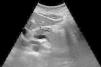

Pancreatitis aguda como síntoma inicial de un tumor de célula pequeña pulmonar

Acute pancreatitis as an initial symptom of a small-cell carcinoma of the lung